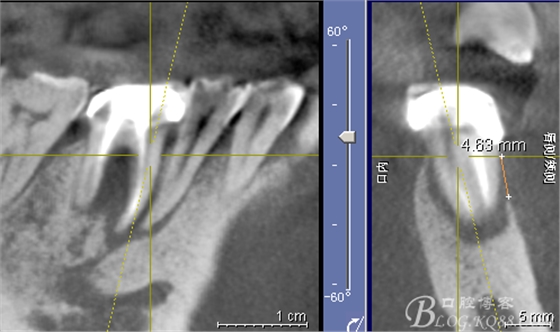

CT可見根管內(nèi)有白色顯影物和根周較大暗影

從根管影像看治療還是不錯的,

懷疑牙根微裂,